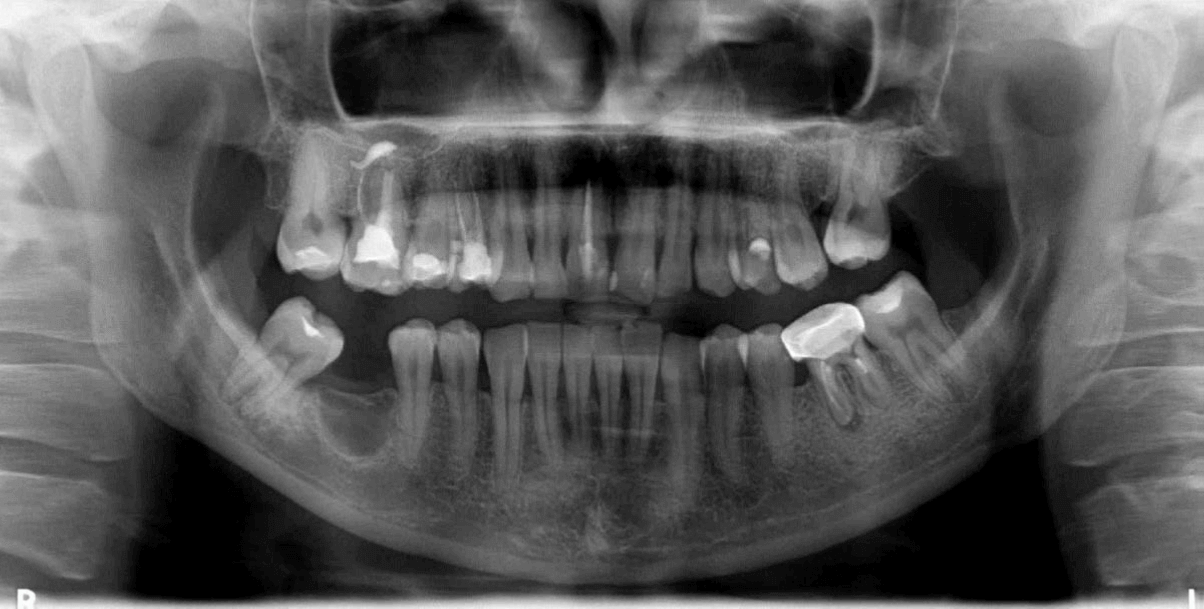

La sustitución dental con una restauración soportada por implantes es un método de tratamiento predecible y eficaz. Las tasas de éxito a largo plazo están relacionadas con el fenómeno de la osteointegración de los implantes dentales. Sin embargo, el proceso de osteointegración del implante puede verse afectado por factores como la estabilidad primaria del implante, que depende de la geometría del implante, la técnica quirúrgica y el estado del hueso, es decir, la densidad y el volumen óseos. Por lo tanto, un estado óseo insuficiente puede dar lugar a complicaciones clínicas durante la colocación del implante dental o durante el proceso de osteointegración. Una de estas afecciones puede ser el defecto óseo medular osteoporótico focal, lo cual es una zona radiotransparente asintomática que suele descubrirse de forma incidental durante un examen radiográfico. Puede tener diversos tamaños y formas sin expansión del hueso cortical de la mandíbula. El defecto óseo medular osteoporótico focal consiste en médula roja hematopoyética con cantidades variables de médula amarilla grasa. Esta afección suele encontrarse en la región posterior de la mandíbula en mujeres adultas. Además, el defecto óseo medular osteoporótico focal se localiza principalmente en zonas edéntulas donde se ha realizado previamente una extracción dental. La falta de estabilidad primaria debido a esta condición puede provocar el desplazamiento o incluso la migración del implante hacia la mandíbula.

Fig.1

El tratamiento consta en rellenar el foco osteoporótico con sustituto óseo y atornillar el implante a nivel tisular, que tiene un cuello y un hombro. Se eligió este tratamiento para evitar posibles complicaciones relacionadas con la lesión del nervio alveolar inferior y el desplazamiento del implante hacia la médula ósea mandibular. Algunos autores presentaron datos sobre el desplazamiento accidental del implante hacia el espacio medular del cuerpo mandibular en pacientes con defecto óseo medular osteoporótico focal. El desplazamiento importante del implante puede causar principalmente la compresión o incluso la lesión del nervio alveolar inferior. La situación puede complicarse con una nueva intervención quirúrgica para la extracción de los implantes, durante la cual pueden producirse lesiones secundarias en el nervio. La mayoría de los autores de los casos presentados utilizaron implantes a nivel óseo que no estaban suficientemente fijados en la capa cortical de la mandíbula. Por el contrario, en este estudio se utilizó un implante a nivel del tejido con un reborde prominente.